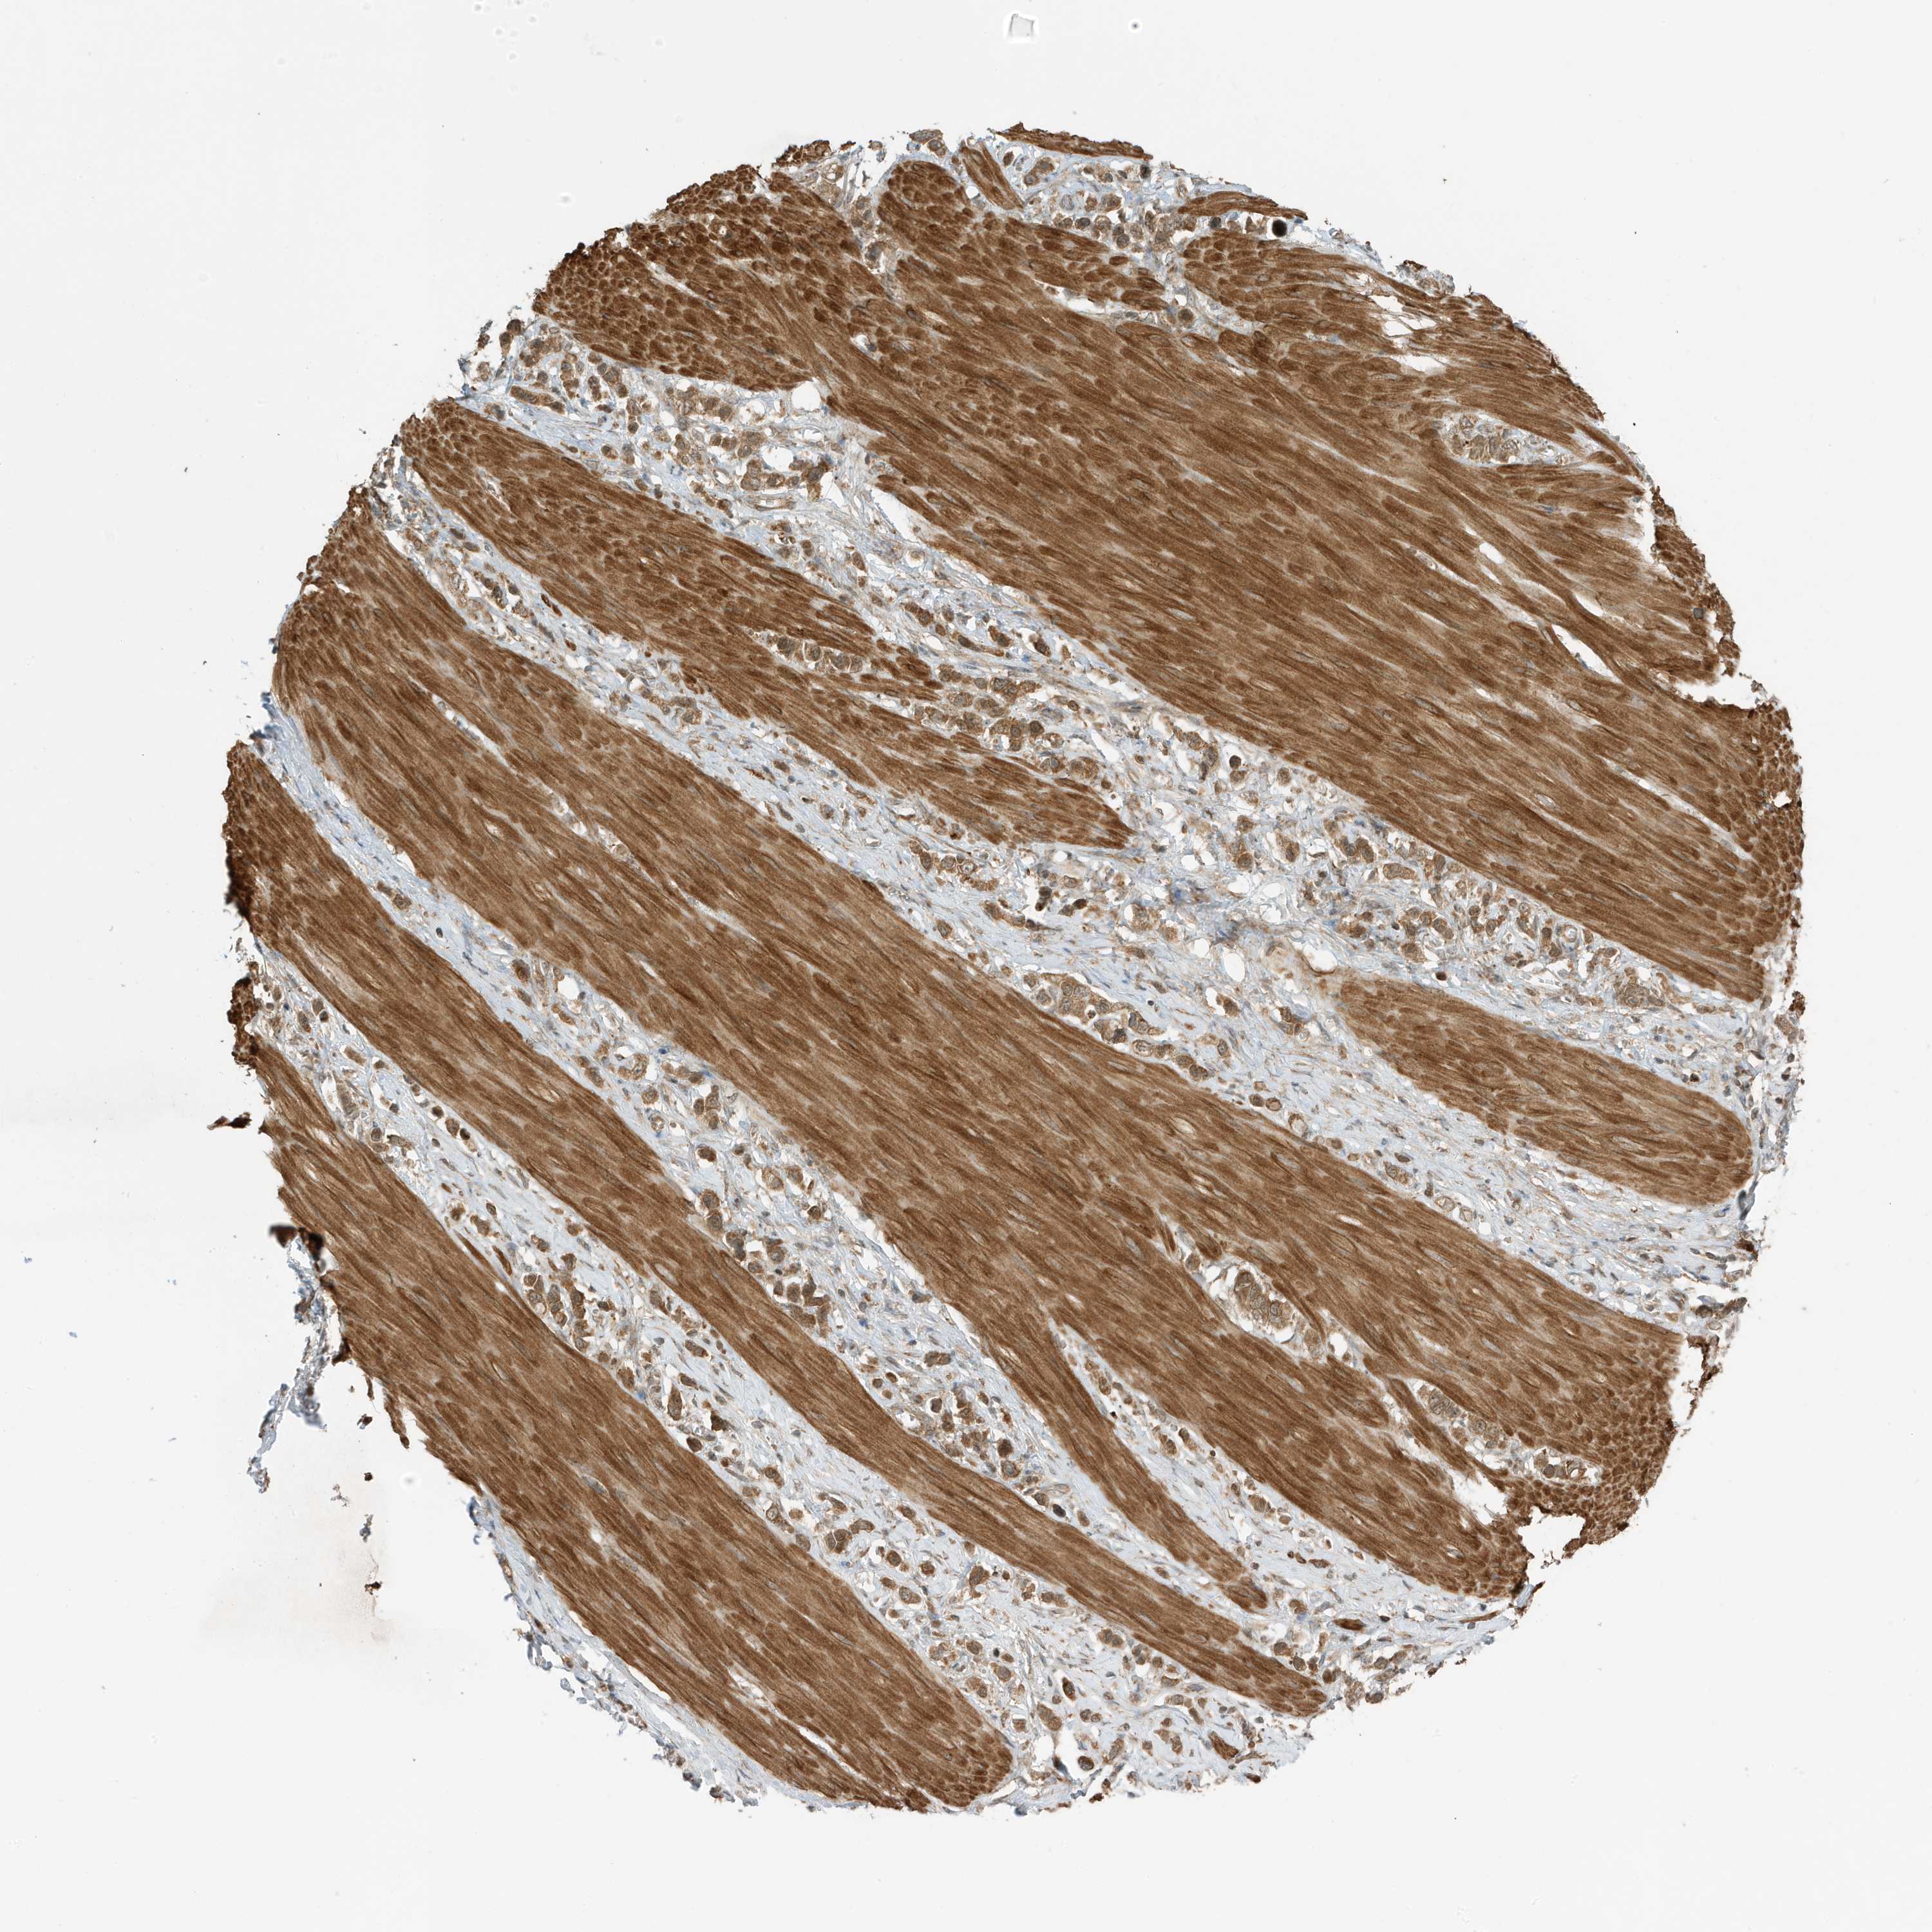

STOMACH CANCER - Protein expressioni

A mouse-over function shows sample information and annotation data. Click on an image to view it in a full screen mode. Samples can be filtered based on level of antibody staining by selecting one or several of the following categories: high, medium, low and not detected. The assay and annotation is described here.

Note that samples used for immunohistochemistry by the Human Protein Atlas do not correspond to samples in the TCGA dataset.

Antibody stainingi

Antibody staining in the annotated cell types in the current human tissue is reported as not detected, low, medium, or high, based on conventional immunohistochemistry profiling in selected tissues. This score is based on the combination of the staining intensity and fraction of stained cells.

Each image is clickable and will lead to virtual microscopy that enables deeper exploration of all samples and also displays staining intensity scores, fraction scores and subcellular localization as well as patient and tissue information for each sample.

Antibody HPA035399

Staining

High

Medium

Low

Not detected

Intensity

Strong

Moderate

Weak

Negative

Quantity

>75%

75%-25%

<25%

None

Location

Nuclear

Cytoplasmic/membranous

Cytoplasmic/membranous,nuclear

Adenocarcinoma, NOS